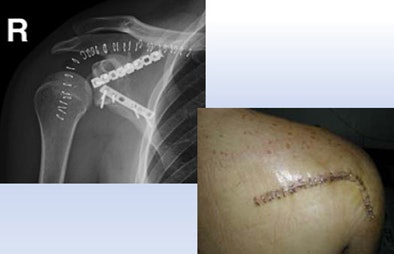

| A 23-year-old man presented with a dramatic fracture of the right scapula from an elevator accident (above). Use of a 3D model allowed surgeons to actually cut the scapula model and carefully design the plates to be implanted (below) before the patient was taken to surgery, leading to a shorter operation time and a successful outcome (bottom image). All images courtesy of Dr. Jacob Sosna. |